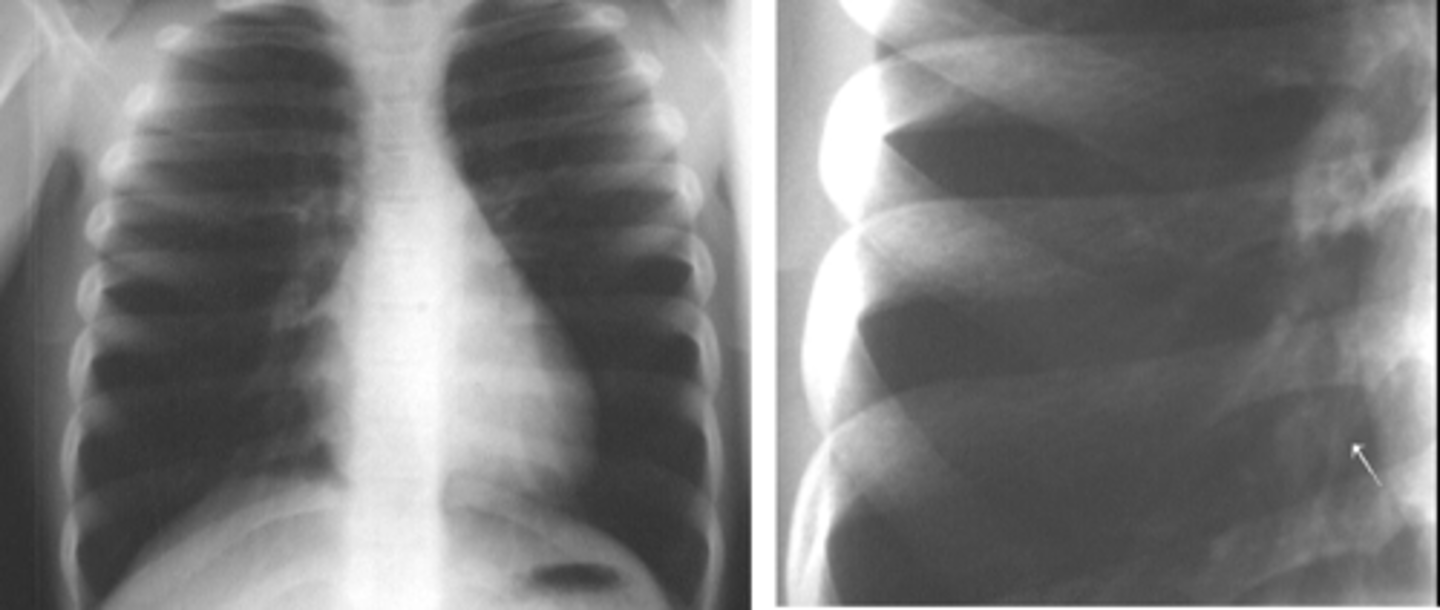

Diaphragmatic rupture

o Usually due to trauma – more common on the left side. Can be a post-op complication of upper GI surgery.

o Most common appearance is loops of bowel in the lower chest cavity (R lung in pic)

-Can cause mediastinal shift

Dx. What is the most common radiologic finding for this dz state?

<p>Dx. What is the most common radiologic finding for this dz state?</p>

New cards

Dx

<p>Dx</p>

Diaphragmatic rupture/hernia

-GI goes to area of least resistance